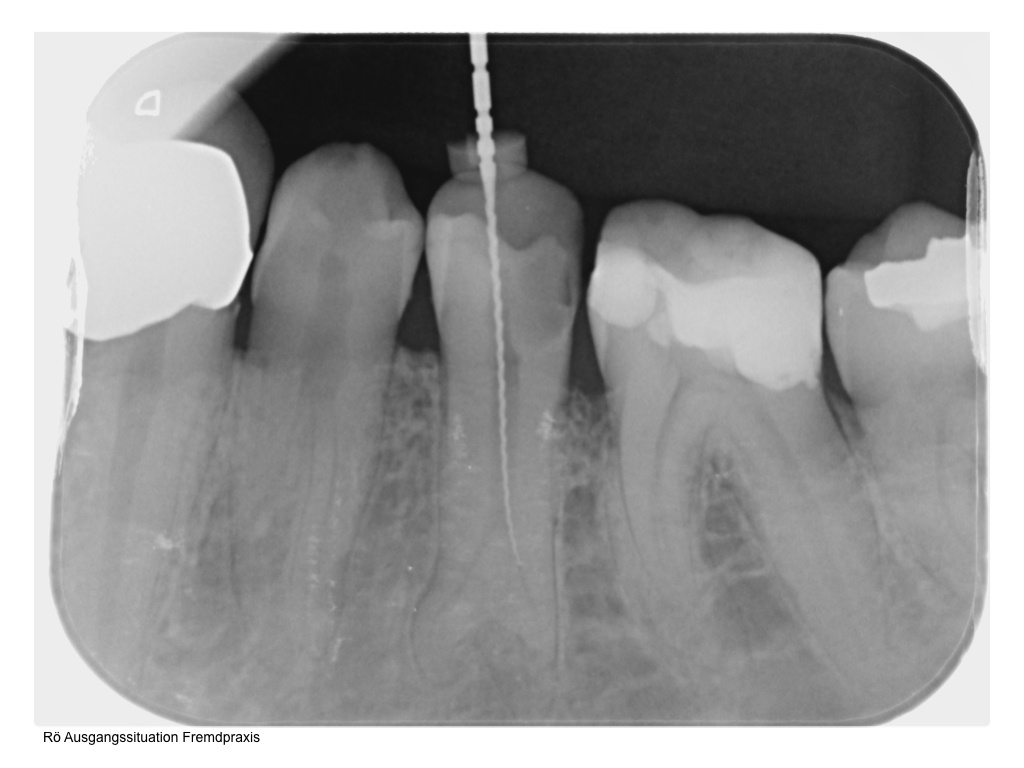

WS_Fallvorstellung15_12_2.001 Veröffentlicht 6. Dezember 2015 am 1024 × 768 in 2015 Fallvorstellung 1